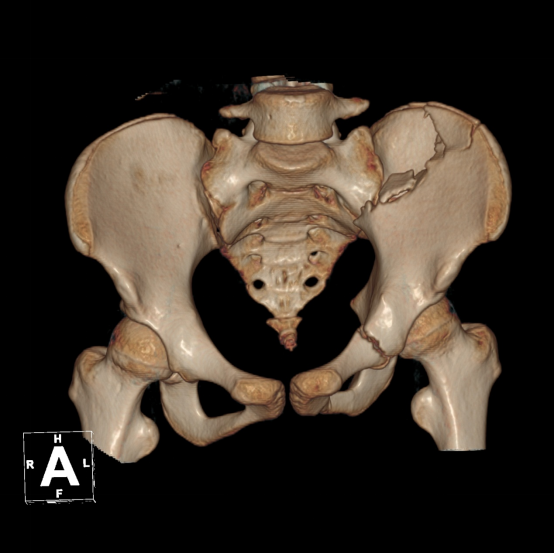

▲术前CT示骨盆骨折完整性被破坏

骨科主任张成勇、副主任许锦涛带领团队细心研判,考虑到患者全身多发骨折,其中骨盆(Tile B2.1型)、腰椎及左踝关节需手术治疗,征得患者家属知情同意后,先行骨盆骨折手术治疗。